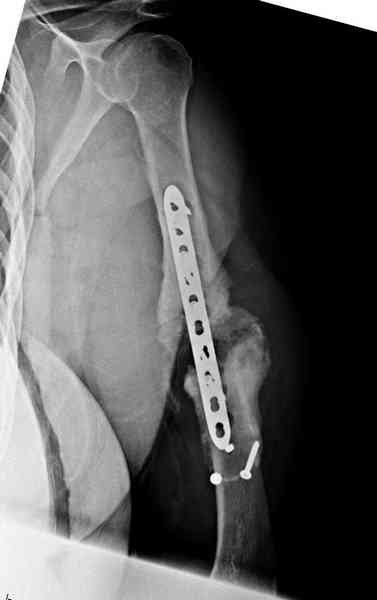

Хотя сам не стороннник применения более массивных имплантов для

плеча, но для этого случая сделали исключение. На снимке 4А диаметр

мягких ткани около 20 см, при весе больной более 135 кг, и также

выступление Андрея Волны подстегнуло к применению более массивной 4.5

мм локинг пластины.